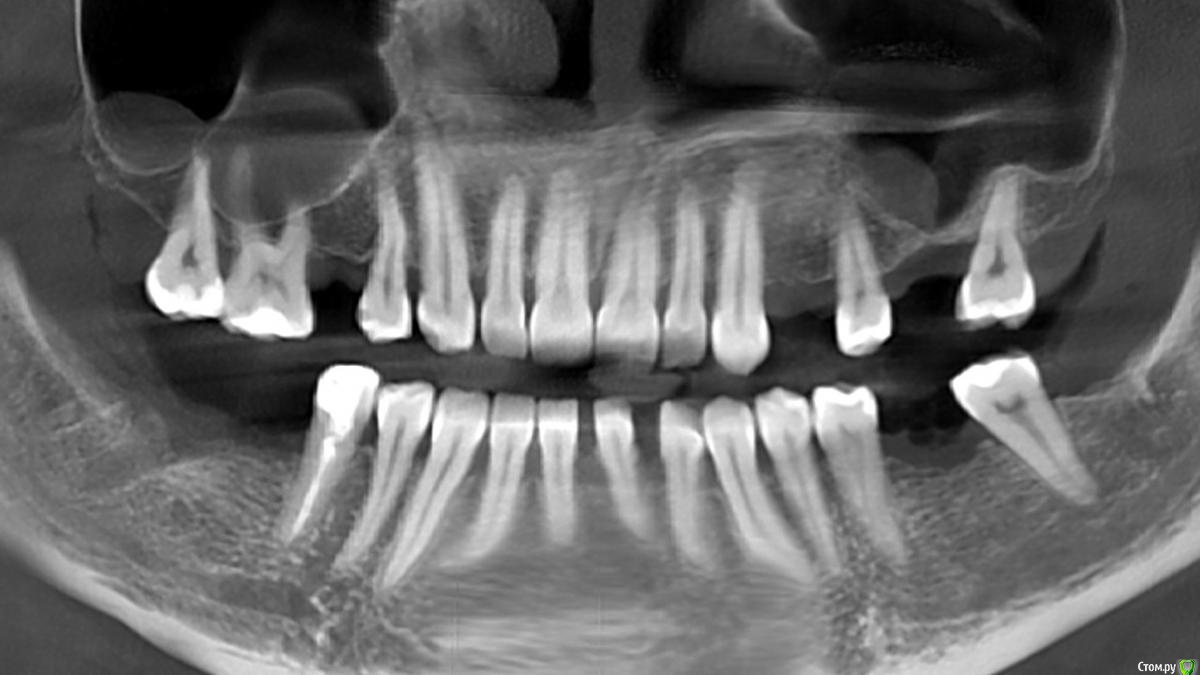

red_butler Опубликовано 26 апреля, 2017 Поделиться Опубликовано 26 апреля, 2017 Это 2D реконструкция, а не панорамный снимок. По тому что Вы выложили , понятно что на нижней челюсти проблем с высотой нет, а в синусах мукоцеле. Для ответов на вопросы нужно смотреть всю Кт и Вас лично. Ссылка на комментарий

red_butler Опубликовано 26 апреля, 2017 Поделиться Опубликовано 26 апреля, 2017 Исправляюсь, в синусе похоже на ретенционные кисты. Ссылка на комментарий

Bier Опубликовано 27 апреля, 2017 Поделиться Опубликовано 27 апреля, 2017 ретенционные кисты не требуют лечения и не мешают проведению имплантации.По нижней челюсти высота кости есть, ширину без полного КТ не увидеть. Но качать его не у всех есть желание. Ссылка на комментарий